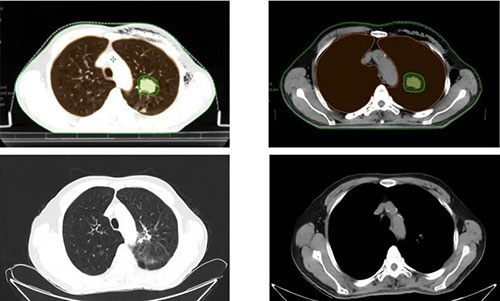

杨哲介绍,省立医院肿瘤放疗科接诊了一位特殊的老年患者——72岁的左肺腺癌(cT1cN0M0 IA3期)男性患者。因该患者高龄、合并重度呼吸功能障碍及高血压等基础疾病,失去了手术机会。肿瘤放疗科综合评估患者情况后制定了SABR的治疗方针,患者在8天内6次放疗后出院,治疗后1个月肿瘤开始缩小,一年后复查,病灶较前明显退缩(如下图)。